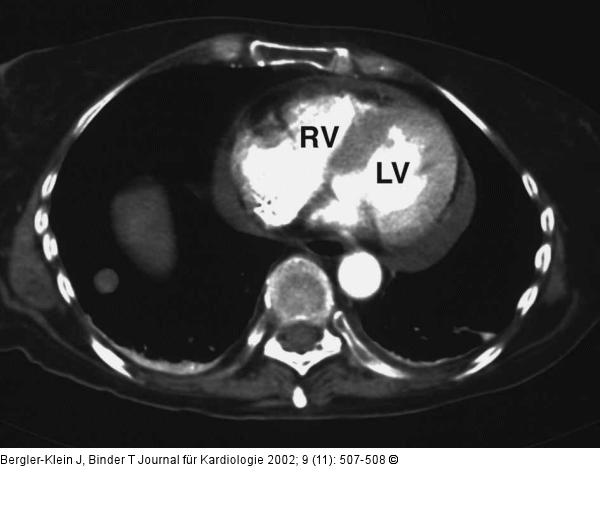

Abbildung 3: Metastasiertes Melanom - Kardiale Manifestation Computertomographie: Auch in der Computertomographie findet sich ein auffallend unregelmäßig begrenztes Myokard; LV = linker Ventrikel; RV = rechter Ventrikel, zusätzlich intrapulmonale Rundherde. |

Abbildung 3: Metastasiertes Melanom - Kardiale Manifestation

Computertomographie: Auch in der Computertomographie findet sich ein auffallend unregelmäßig begrenztes Myokard; LV = linker Ventrikel; RV = rechter Ventrikel, zusätzlich intrapulmonale Rundherde. |